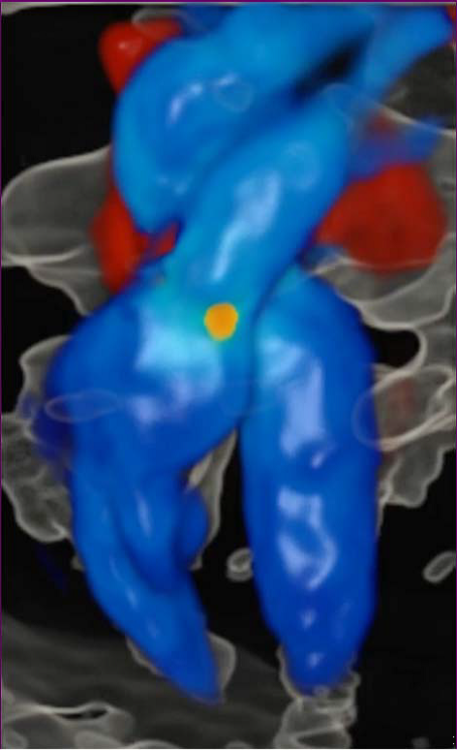

Снимок развития сердца, сделанный в первый триместр беременности с помощью приложения HDlive Flow.

Снимок развития сердца, сделанный в первый триместр беременности с помощью приложения HDlive Flow.Подобным быстродействием система обязана новым датчикам, изготовленным по технологии Electronic 4D. В датчике установлены более 8000 пьезокристаллов для электронного управления ультразвуковым пучком и обеспечения четкости и скорости.

Неподвижное изображение ноги, полученное с помощью ультразвука в режиме 4D в приложении HDlive Silhouette.Еще одна функция программного обеспечения HDlive Flow — это создание 3D-изображения потока крови и фотореалистичного изображения кровеносных сосудов. «Такая возможность очень важна для врачей, когда они рассматривают патологические изменения, — говорит Барбара Дель Принс. — Однако большинство родителей, скорее всего, просто запомнят первую улыбку своего ребенка».